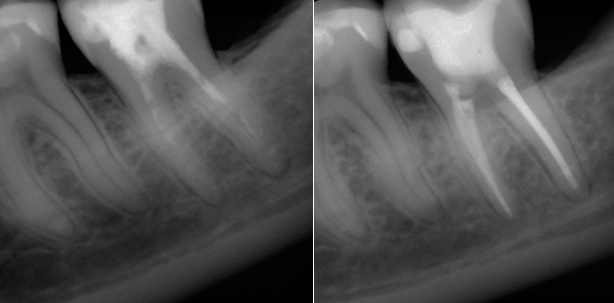

Nach der konventionellen Aufbereitung, Reinigung und Desinfektion der Wurzelkanäle kommt der Laser zum Einsatz (Abb. 1 bis 6). Hierbei wird die Laserfaser auf die vorher bestimmte Arbeitslänge eingeführt und anschließend unter kreisenden Bewegungen ca. 1 mm pro Sekunde nach koronal aus dem Kanal gezogen. Dadurch wird das gesamte Wurzeldentin bestrahlt. Dieser Vorgang wird mit einer entsprechenden Pause in der Regel fünf Mal wiederholt, um auch in den tieferen Wurzeldentinschichten eine sichere Dekontamination zu erzielen. Neben der entsprechenden Parameterwahl (zumeist vom Hersteller schon als Vorauswahl im Anwendungsmenü der Laser hinterlegt) ist nur darauf zu achten, nicht zu lange am apikalen Stopp zu verbleiben, um einen unerwünschten Hitzeeintrag in das umliegende periapikale Gewebe zu verhindern.